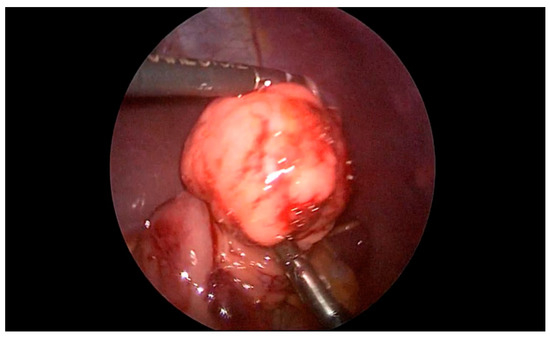

Our eighth case is a 9-year-old boy who was admitted to the clinic for pediatric surgery for the planned polypectomy of the stomach. Gastroduodenoscopy revealed a submucosal polypoid formation with a diameter around 1.5 cm in the region of the pylorus. The child was referred to a pediatric surgeon. Under the guidance of endoscopist, a laparoscopic gastrotomy and polypectomy was performed in the way already described (Figure 5). The polyp was sent for histological evaluation and gastroplasty with omentopexy was performed. The histological evaluation revealed pancreatic tissue ectopy in the stomach.

Figure 5. Laparoscopic gastrotomy and polypectomy (pancreatic tissue ectopy in the stomach) under the guidance of endoscopist.